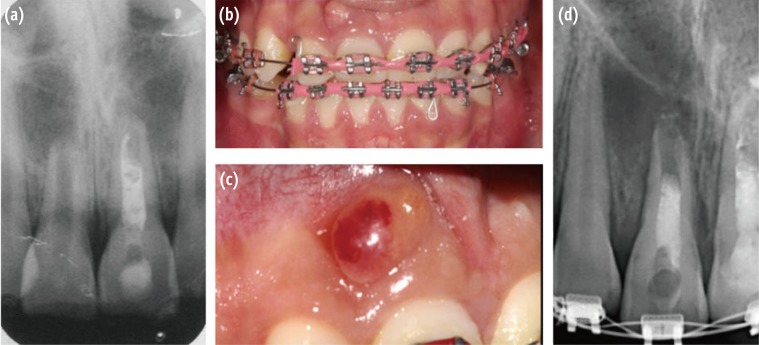

At 3 and 6 months follow-up, the patient was asymptomatic, and slight healing of the apical radiolucency was noticed (Figures 4a and 4b). The orthodontist was advised to use no force on the tooth. At the 12 months follow-up appointment, the patient remained asymptomatic, and the orthodontic appliances were removed. Radiographic examination demonstrated evidence of periradicular bone healing (Figure 4c). At the 3 year recall appointment, the patient was asymptomatic, and a periapical radiograph showed disappearance of the apical radiolucency and closure of the root apex (Figure 5a). The treatment outcome was confirmed with cone beam computed tomography (CBCT) images (Figures 5b and 5c).

Figure 4

Follow-up radiographs of tooth #11 at (a) 3 months; (b) 6 months; (c) 12 months.

Figure 5

Three year follow-up confirming the healing process. (a) Conventional radiograph; (b) CBCT three-dimensional reconstruction; (c) CBCT buccal view. CBCT, cone beam computed tomography.

Figure 4 Follow-up radiographs of tooth #11 at (a) 3 months; (b) 6 months; (c) 12 months.

Figure 5 Three year follow-up confirming the healing process. (a) Conventional radiograph; (b) CBCT three-dimensional reconstruction; (c) CBCT buccal view. CBCT, cone beam computed tomography.